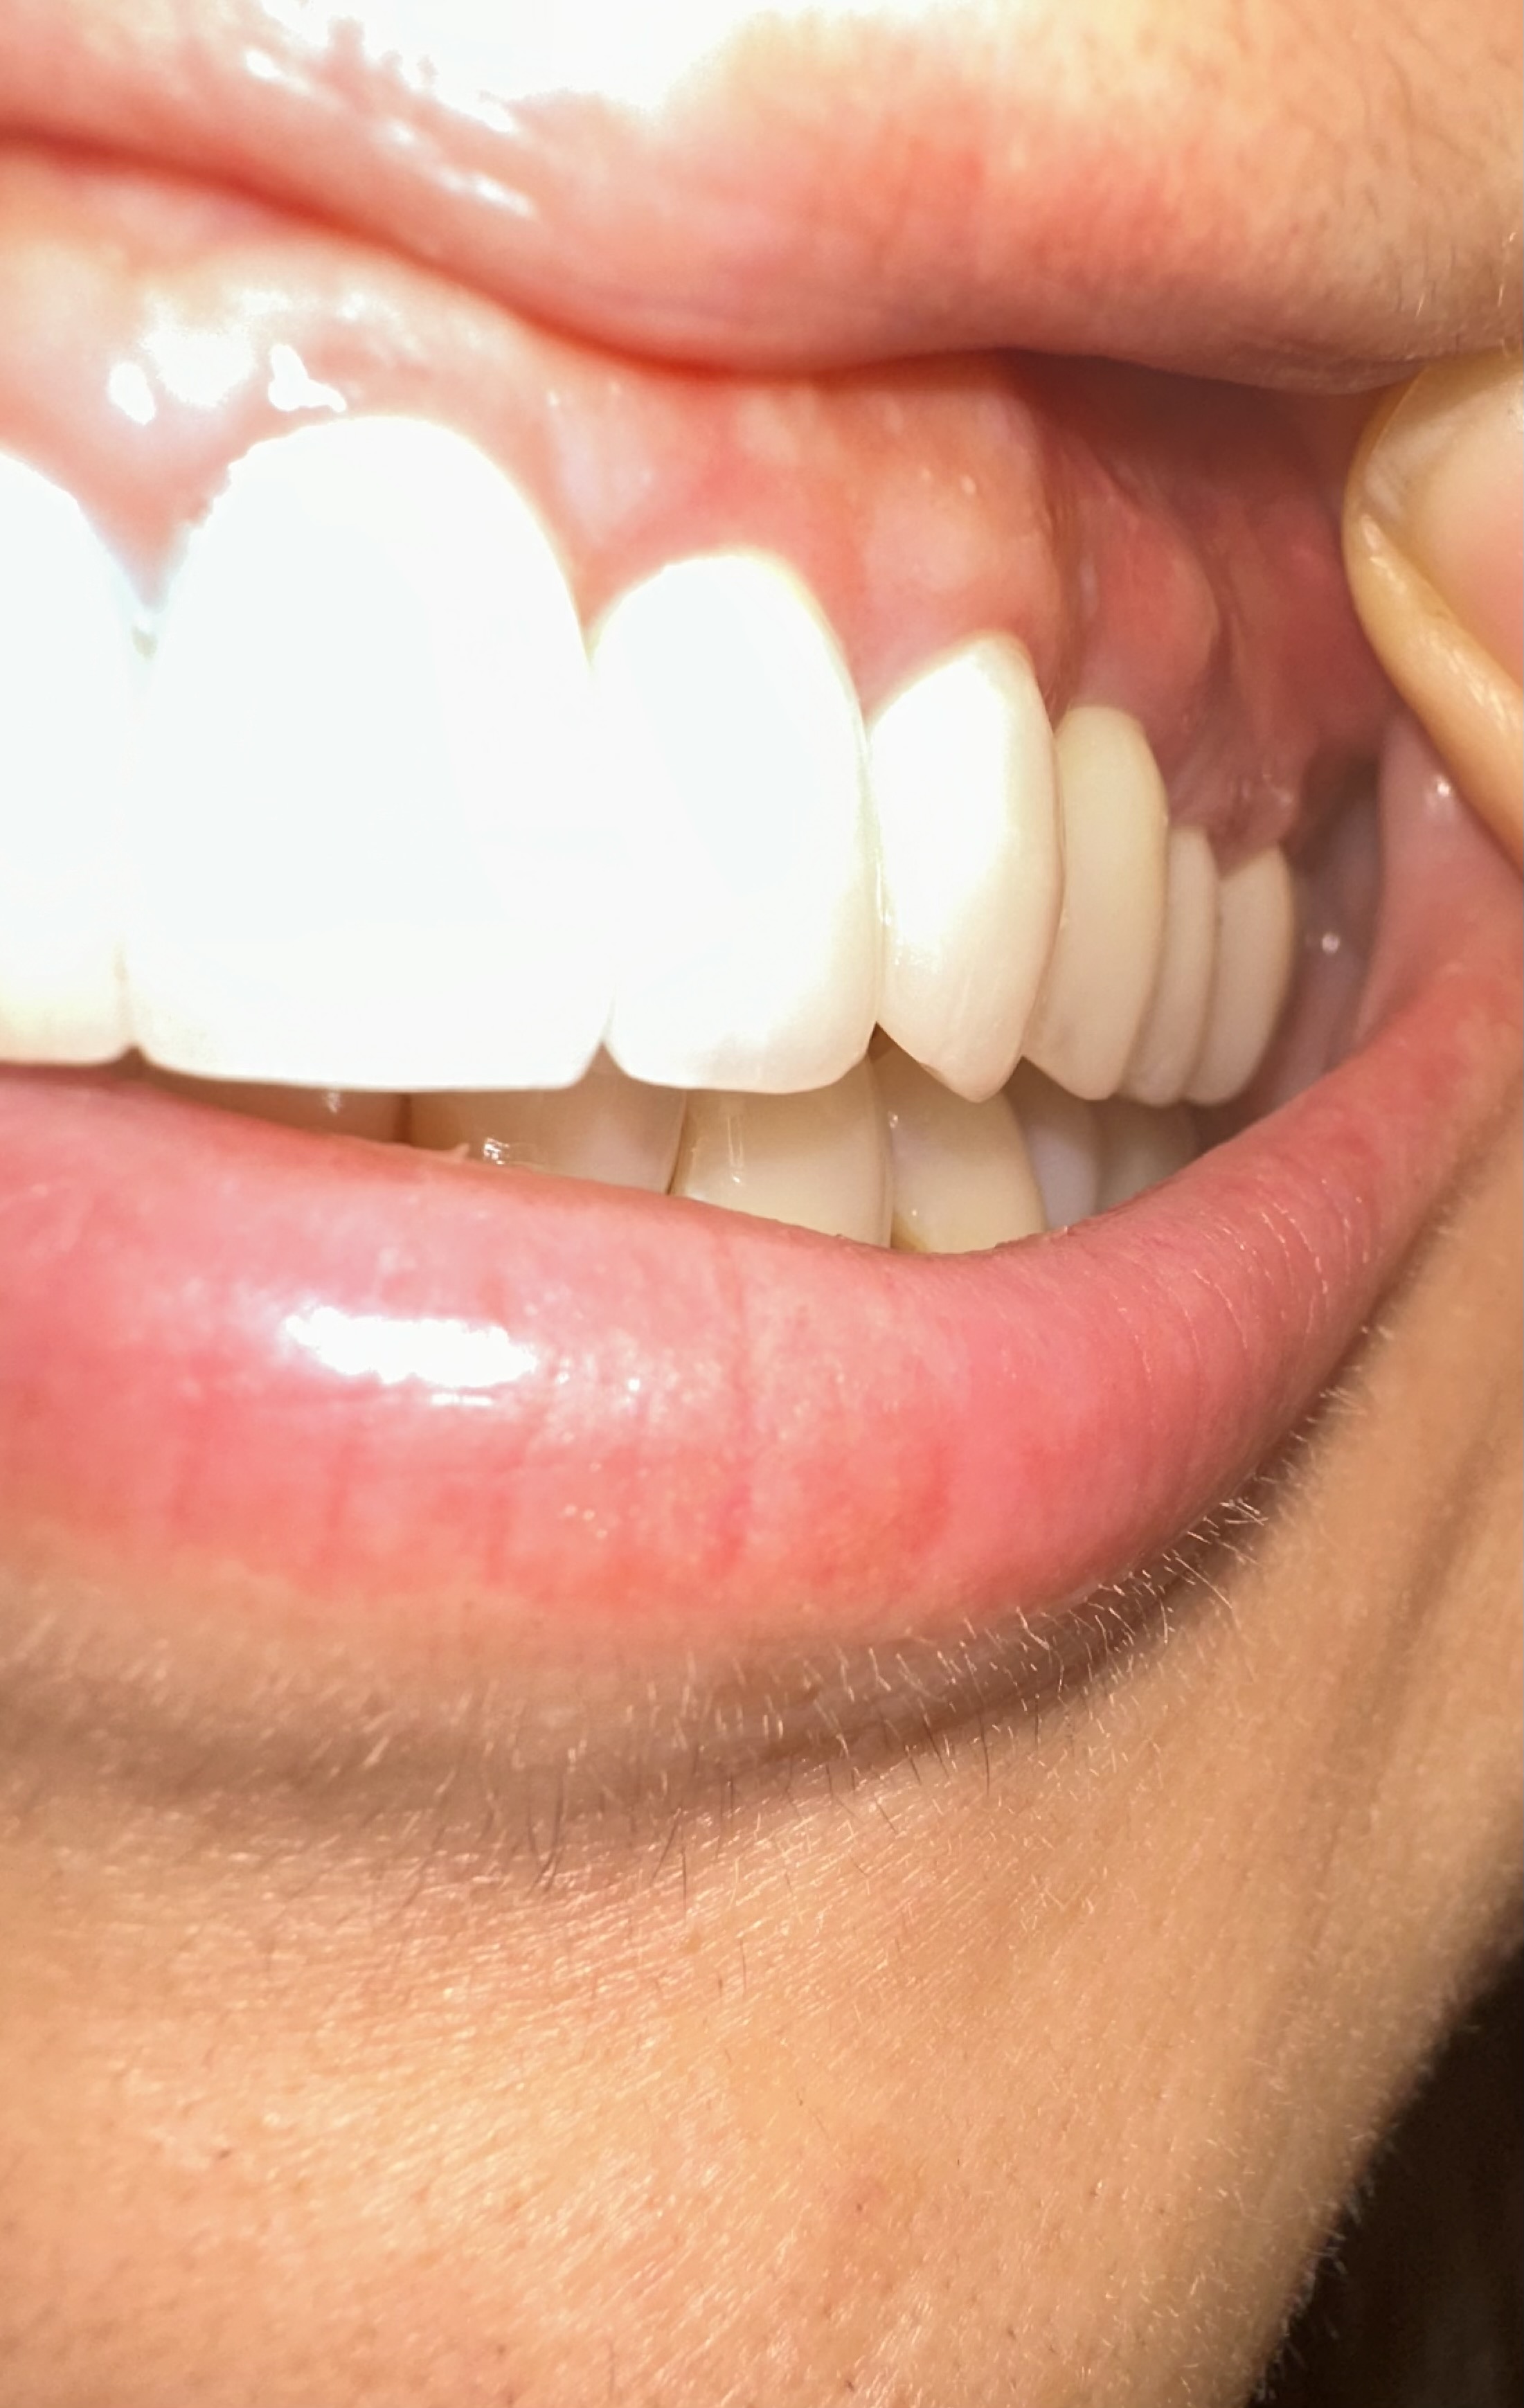

こんにちは。左上犬歯に相当する部位に関してでしょうか?現状を再度みていただいた方が良いのではないかと思います。

フィステルのようなものができているのは、調べたところ「第一小臼歯」の上でした。

今日また歯医者さんに行き、針のような器具を挿入した状態でレントゲンを撮ってもらいました。その結果、針がインプラントの手前で曲がっていたため、原因はインプラントの歯ではなく、別の歯にあるとのことでした。

先生のお話では、このできものはフィステルであるとのことで、原因としては側切歯の根の部分に炎症があるのでそこの歯からの可能性が高いそうです。とりあえず担当医と相談するように言われましたが、担当医は現在休暇中のため、次回の予約は11月20日になっています。

今回のフィステルが二つ隣の歯にできるということは本当にあるのでしょうか?